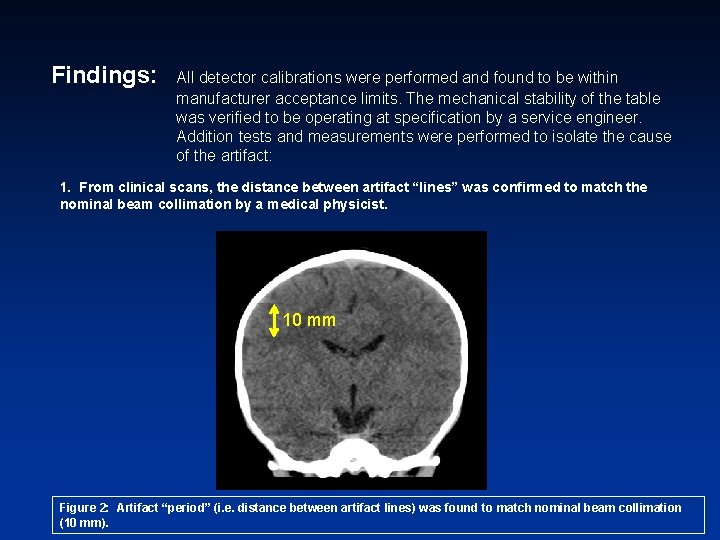

Findings: All detector calibrations were performed and found to be within manufacturer acceptance limits. The mechanical stability of the table was verified to be operating at specification by a service engineer. Addition tests and measurements were performed to isolate the cause of the artifact: 1. From clinical scans, the distance between artifact “lines” was confirmed to match the nominal beam collimation by a medical physicist. 10 mm Figure 2: Artifact “period” (i. e. distance between artifact lines) was found to match nominal beam collimation (10 mm).